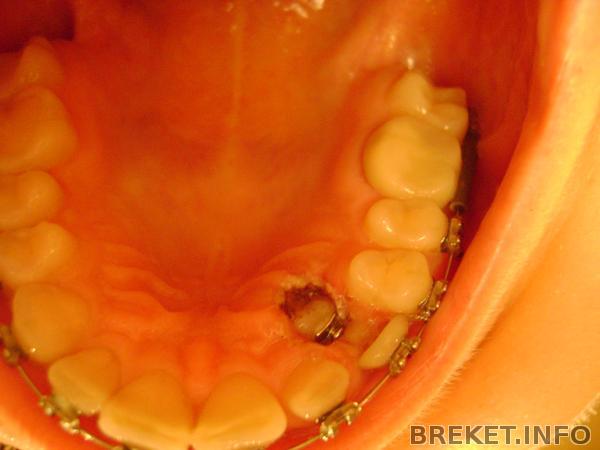

как все было до. Сразу в глаза бросается ужасно маленький клык